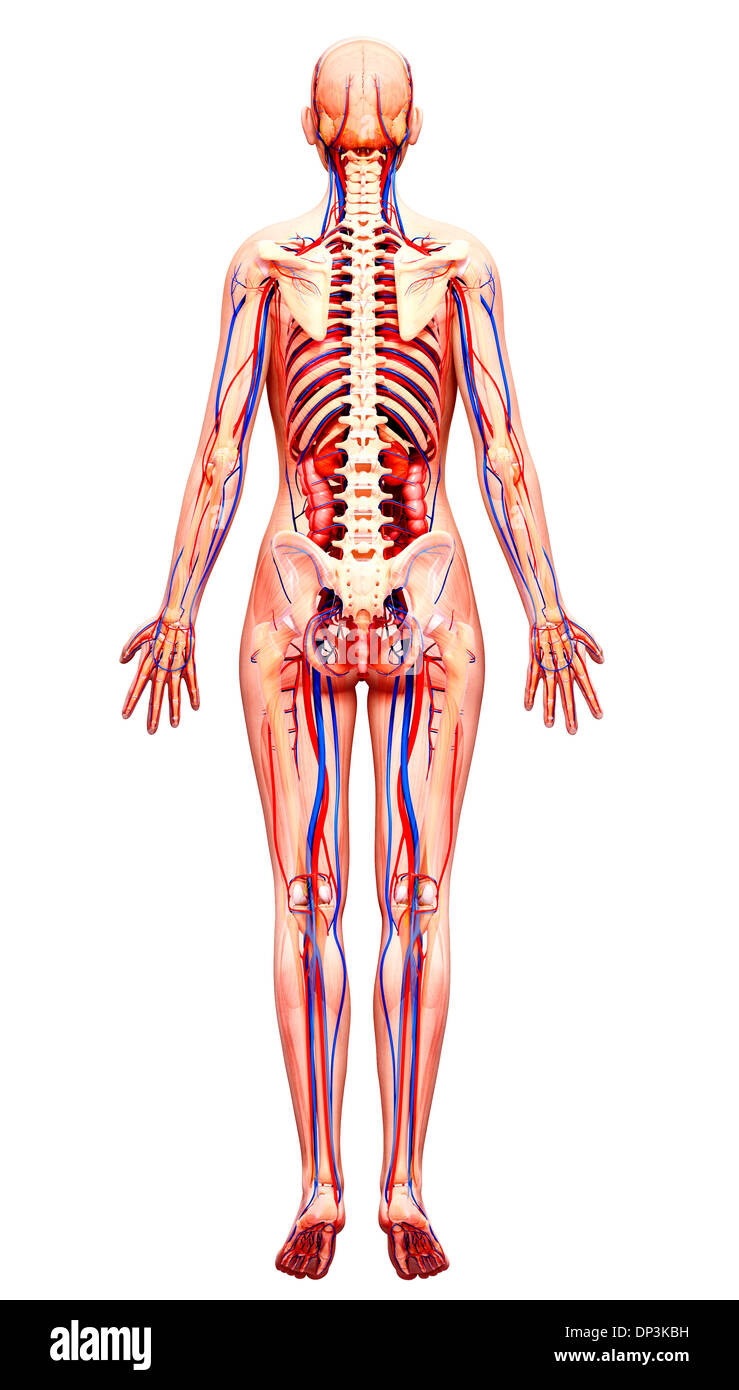

Système cardiovasculaire, artwork Banque D'Imageshttps://www.alamyimages.fr/image-license-details/?v=1https://www.alamyimages.fr/photo-image-systeme-cardiovasculaire-artwork-55415491.html

Système cardiovasculaire, artwork Banque D'Imageshttps://www.alamyimages.fr/image-license-details/?v=1https://www.alamyimages.fr/photo-image-systeme-cardiovasculaire-artwork-55415491.htmlRFD64B0K–Système cardiovasculaire, artwork